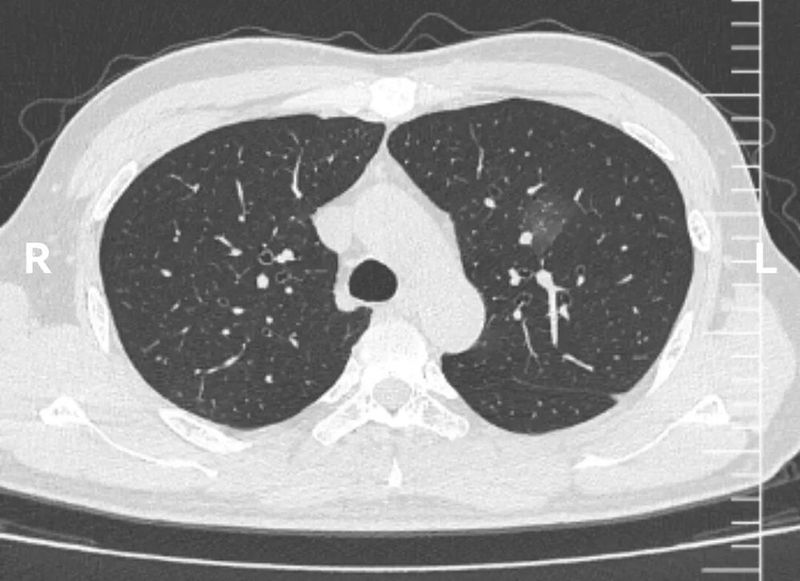

1个月后复查CT,该结节如愿明显吸收。